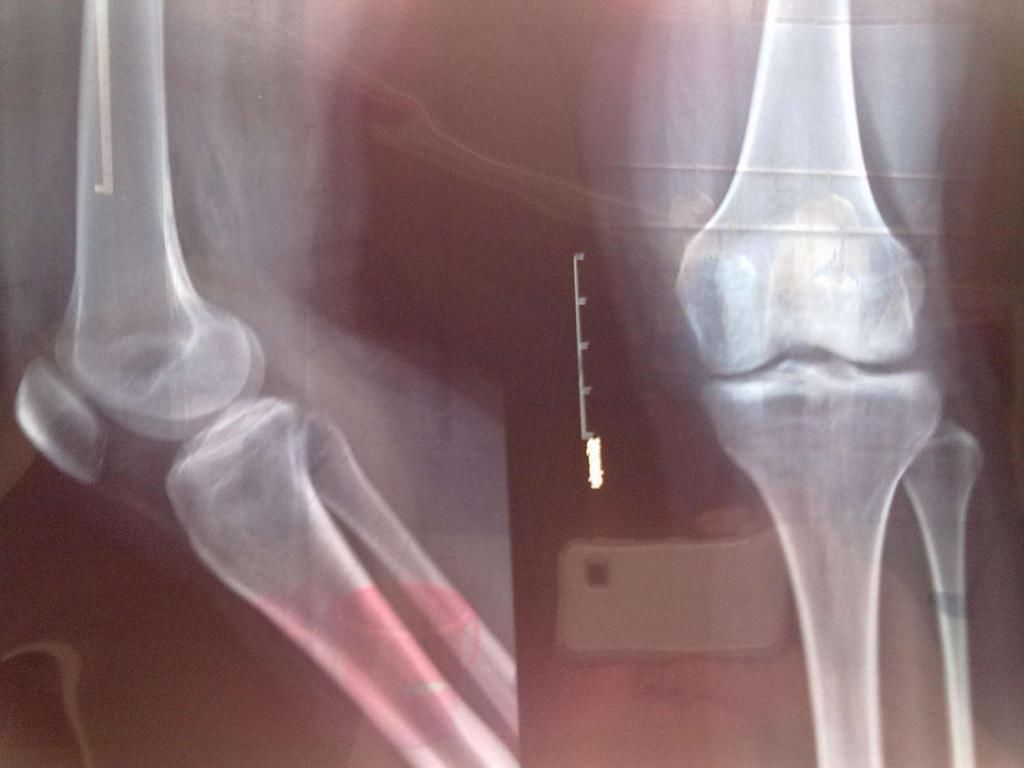

2、骨骺线未闭合大家都知道骨骺线是骨骼发育的重要标志,对于一个人来说,腿部的骨骺线如果完全闭合,那么他就失去了自然长高的可能性,他们的身高也就不会再发生变化。

每个人的骨骺线闭合时间不确定,如果一些年轻女性怀孕的时候骨骺线还没有完全闭合,那么她们在怀孕期间,因为休息充足、营养比较多,所以她们非常有可能出现“生娃窜一窜”的现象,身高也会变得更理想。